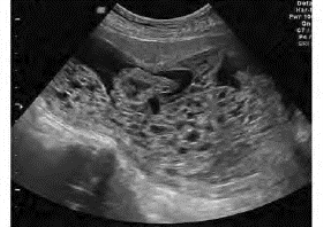

(2)宫腔内充满小囊泡样无回声区,似“落雪花状或蜂窝状”,大小不等,0.2~1.0cm,大者形态多不规则,囊泡间回声一般较强(图34-13)。

图34-13 葡萄胎声像图

子宫内充满大小不等的水泡样回声,未见正常胎儿图像